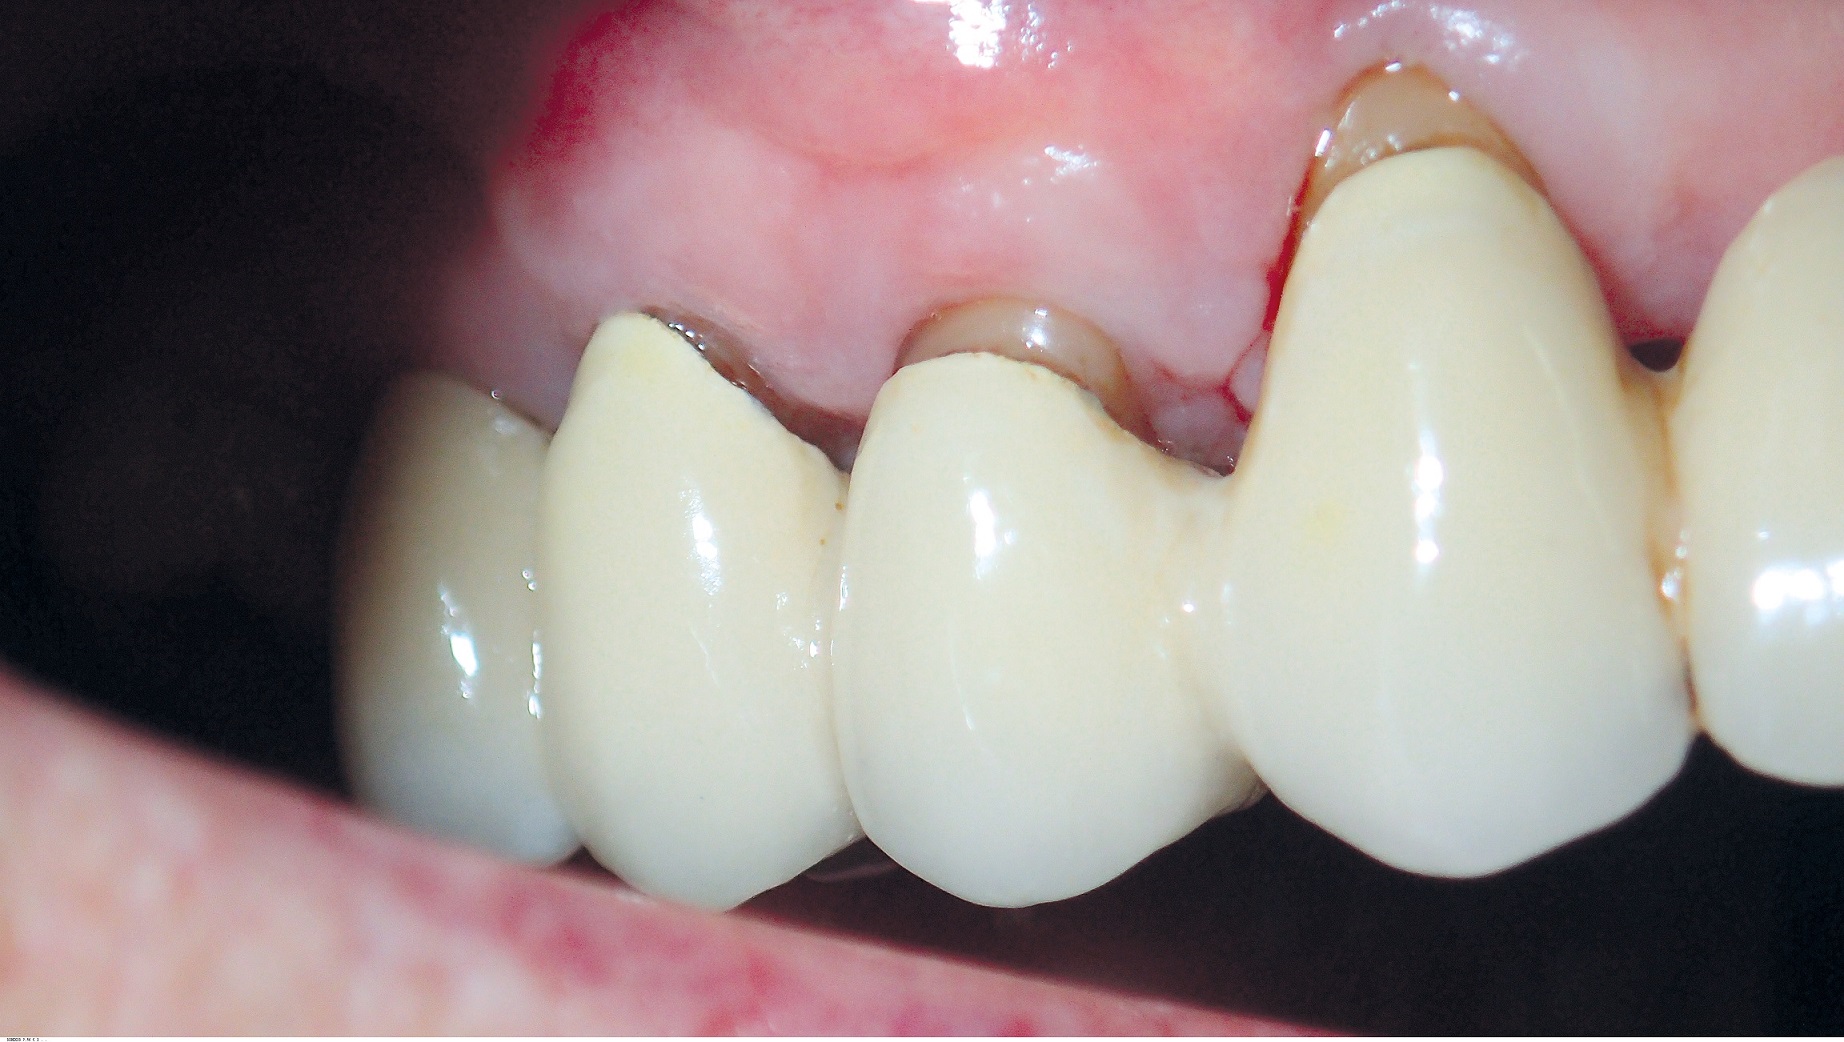

09/10 - Stable clinical situation 6 months post-operative.GTR for the treatment of a deep three-dimensional intrabony defect using cerabone®, collprotect® membrane and Straumann® Emdogain® - Dr. T. Schwaar